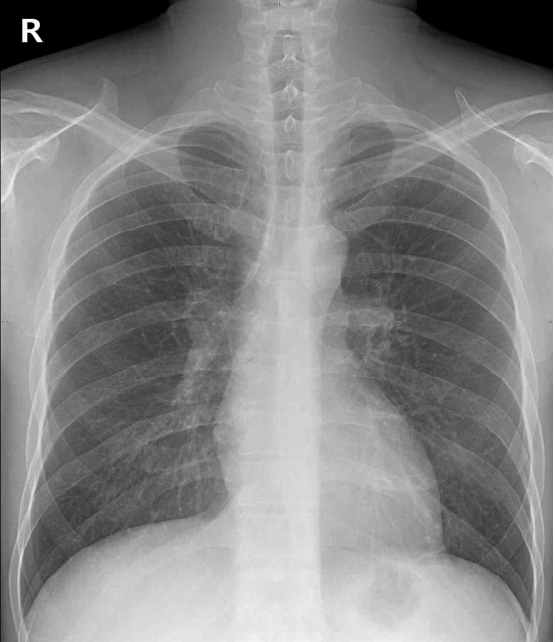

30세 남자가 5개월 전부터 빨리 걸을 때 숨이 차서 병원에 왔다. 혈압 125/84 mmHg, 맥박 50회/분, 호흡 16회/분, 체온 36.7°C이다. 복장뼈 왼쪽 3번째 갈비사이공간에서 3/6도의 수축기 잡음이 들린다. 가슴 X선사진과 심전도이다. 심초음파검사 결과는 다음과 같다. 진단은?

CXR: No remarkable findings

복장뼈 왼쪽 3번째 갈비사이공간에서 3/6도의 수축기 잡음, 심초음파 상 심실중격 두께 및 LVOT gradient의 증가, ECG의 LV hypertrophy 및 giant T wave inversion을 통해 비대심근병증으로 진단한다.